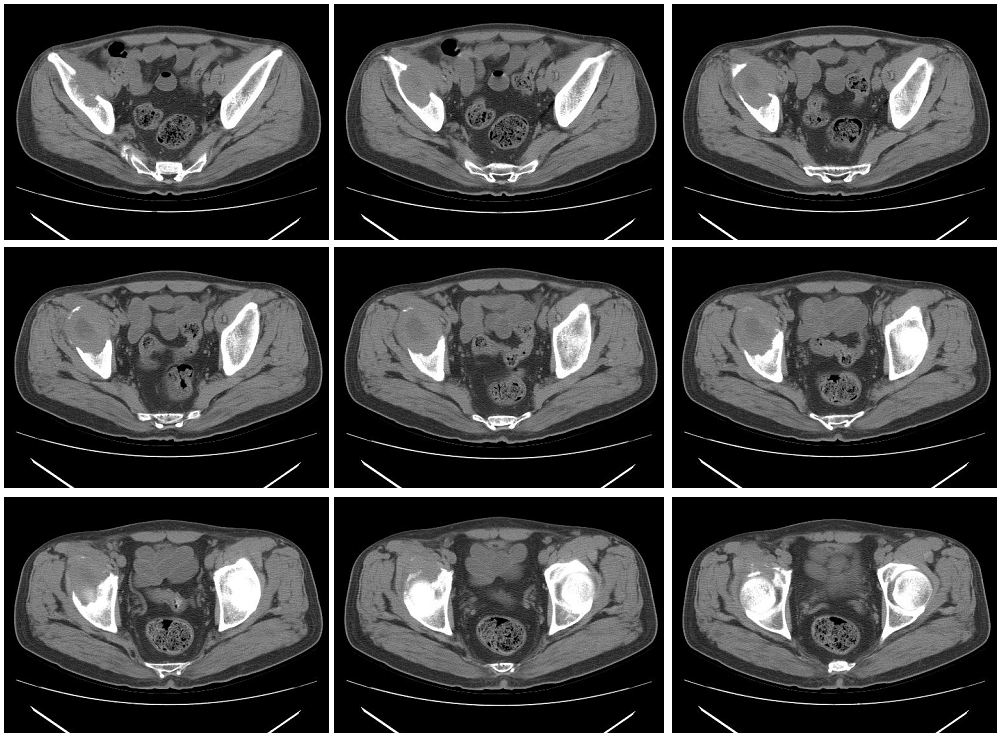

男性,57岁,右髋部疼痛一月

骨质破坏严重,考虑恶性肿瘤。

溶骨性破坏,并软组织肿块,恶性肿瘤,转移瘤可能性大。

右髂骨中心性溶骨性膨胀破坏,但边界尚清,不排外良性可能

右侧髂骨溶骨性骨质破坏,且见有软组织肿块,首选考虑转移瘤,其次考虑淋巴瘤或骨肉瘤。